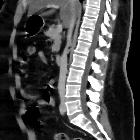

Atemartefakte

in der Computertomographie: In der sagittalen Rekonstruktion sieht man den alternierenden Versatz der vorderen Bauchwand durch die Atemexkursionen. (Hautgrenze bei Adipositas nicht mit im Bild)